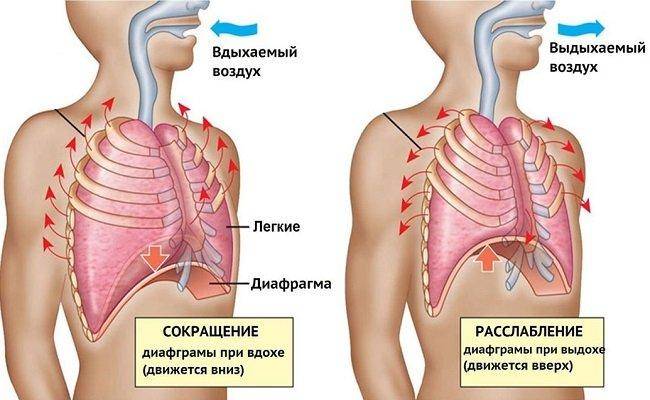

При любом типе дыхания за обработку кислорода отвечают легкие. Но их увеличение, как и изменение объема полости груди, зависит от 2 разных способов:

- При вдохе стенка груди приподнимается и отодвигается от позвоночника, из-за чего полость грудной клетки спереди увеличивается (образуется дополнительный объем между позвоночником и грудиной). В этом процессе участвуют ребра, прикрепленные к позвоночнику под острым углом. Своими концами они формируют дугу, расширяя возможный объем. Так как ребра крепятся к грудной кости, они тянут ее за собой.

- Второй способ зависит от опущения грудобрюшной преграды по направлению книзу. Это – диафрагма, имеющая куполообразную форму. Грудные мышцы отвечают в процессе дыхания за то, чтобы этот купол тянулся вниз, освобождая простор для легких. Середина опускается книзу и создается нужный объем. Из-за опущения грудная часть диафрагмы давит на живот, в результате выпячивается его стенка.

- Диафрагмальное (брюшное), когда в момент вдоха живот выступает вперёд, а на выдохе подтягивается по направлению к позвоночнику.

Главный орган в брюшном дыхании — диафрагма. Диафрагмальная мышца — это куполообразная перегородка, она отделяет грудную клетку от органов, расположенных ниже в брюшной полости. На вдохе диафрагмальная мышца идёт вниз и сжимается, заставляя брюшную стенку выдвигаться вперёд. В момент выдоха диафрагмальная мышца возвращается вверх и приобретает форму купола, выгоняя воздух из лёгких.

На вдохе диафрагма движется вниз, на выдохе — поднимается вверх

На вдохе диафрагма движется вниз, на выдохе — поднимается вверх